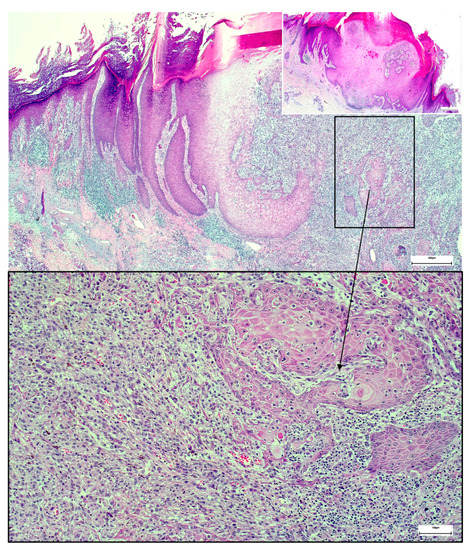

A Wolf in Sheep’s Clothing: Collision of Melanoma and Keratoacanthoma

:1. Case Presentation

2. Discussion